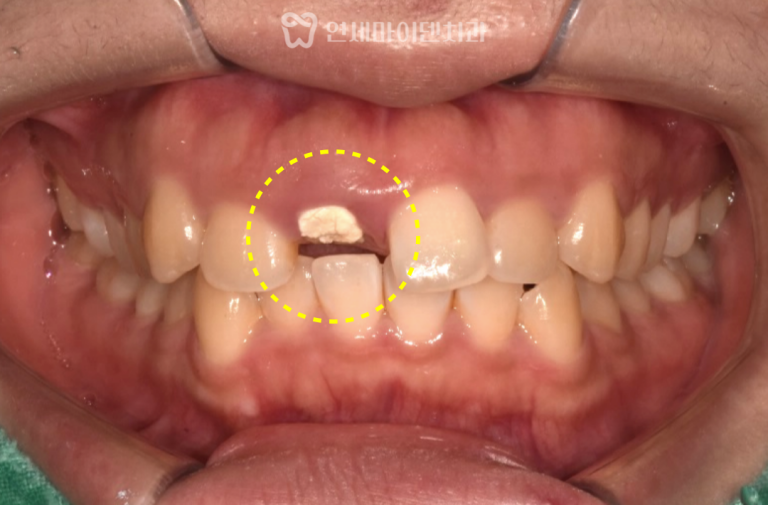

상악 좌측 제2대구치는 초기에는

신경치료 후 크라운 수복까지 완료하였으나,

7개월 후 재내원 시 입천장 쪽 치근 주위의 치조골이

완전히 소실된 상태였습니다.

외측 치근이 정상으로 보여 판단이 어려웠던 케이스로,

세균막이 치근 내면 깊숙이 형성되어 있었습니다.

이 부위는 즉시 임플란트가 불가능하다고 판단하여

우선 발치와 보존술(socket preservation) 을 시행하였습니다.